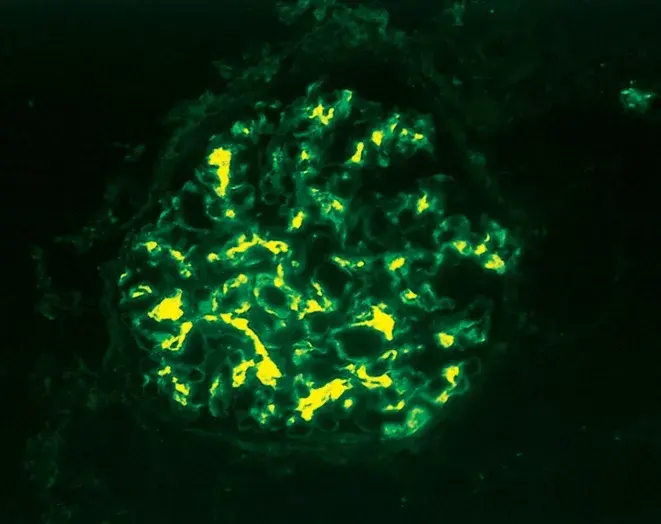

Nefropatia Membranosa: e se o paciente não responder ao tratamento inicial?

Nefropatia Membranosa: e se o paciente não responder ao tratamento inicial?

Neste vídeo, abordamos estratégias para lidar com pacientes com nefropatia membranosa que não respondem ao tratamento inicial. Ele enfatiza a importância da reavaliação constante e do ajuste do regime de tratamento com base nos resultados e no estado do paciente.

Como fazer o tratamento da Nefropatia Membranosa de forma prática!

Como fazer o tratamento da Nefropatia Membranosa de forma prática!